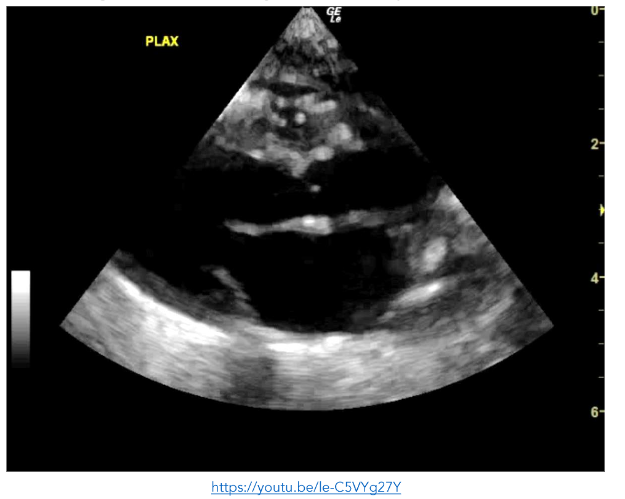

A 9 day-old neonate presented to the ED with his parents who were concerned about progressive lethargy, work of breathing and grunting in the preceding 24 hours. On assessment he was hypotensive, hypoxic and febrile. His neonatal course to date included treatment for Group B-Streptococcus infection following delivery.

On arrival he rapidly deteriorated. His pulse could not be effectively palpated, and cardiac monitoring noted a bradycardia of 50 beats per minute (bpm). As per resuscitative guidelines, chest compressions were commenced. During a rhythm check POCE was ongoing at the time and while contractility was very poor, there were regular organised contractions at a rate of 80 bpm. Compressions were discontinued and the patient was commenced on inotropic support. Another finding from the POCE was the presence of multiple small mobile masses in the right atrium and ventricle, consistent with multiple septic emboli.

Point of care echocardiogram findings helped to guide fluid resuscitation, antibiotics, chronotropic and inotropic support, and rapid sequence induction for hypoxia and cardiogenic shock, including transfer to the paediatric intensive care unit (PICU) within 70 minutes.

Figure 6: PLAX view showing reduced contractility of the left ventricle